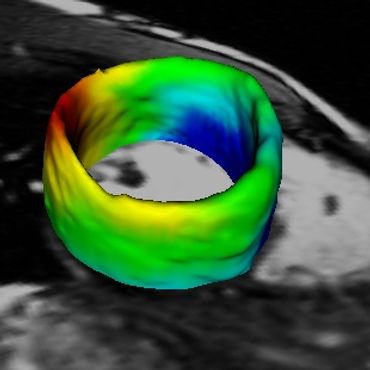

Procesamiento de Imágenes Vectoriales y 4D MRI - Medical Image Analysis (MIA99) (pdf)

DescargarEcocardiografía 3D+T- Transactions on Medical Imaging (TMI02) (pdf)

TODOS LOS CÁLCULOS, IMÁGENES Y ANIMACIONES en esta página y artículos, fueron producidos con PROGRAMAS ESCRITOS POR MI en C / C++ y VTK/TCL/TK